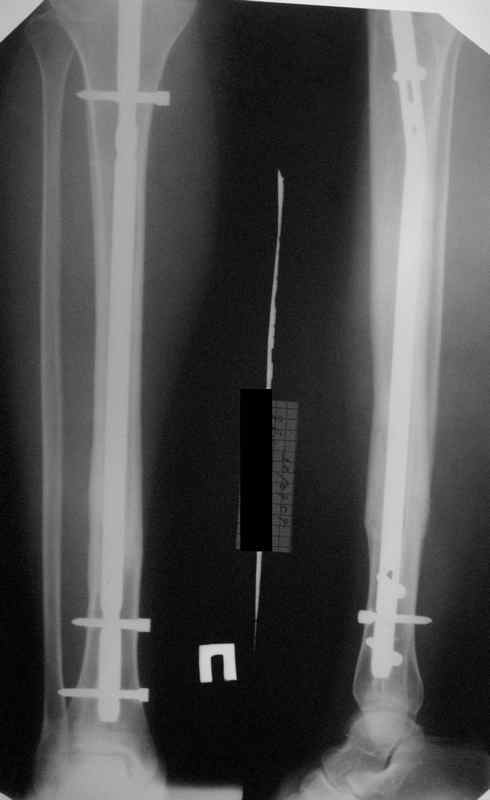

>СА> По Вашему намного реально стало лучше?

По-моему, стало так, как должно быть.

>СА> представленные снимки этому подтверждение-данный кососпиральный

СА> перелом репонируется идеально только открыто,что при БИОС не так существенно.

Здесь проблема не в идеальности репозиции, а в запасе усталостной прочности. Срастаться там может небыстро, диастазы довольно большие.

И когда еще и отломок короткий, и отверстие совсем рядом, это может привести к перелому стержня. За последние годы у нас было несколько пациентов, оперированных в других учреждениях с

подобным положением отломков, с такими переломами гвздей. И сейчас переделать куда как проще и легче, чем иметь дело со сломанным гвоздем.

По крайней мере, при нынешнем положении фиксатора стал меньше риск того, что до сращения гвоздь сломается.